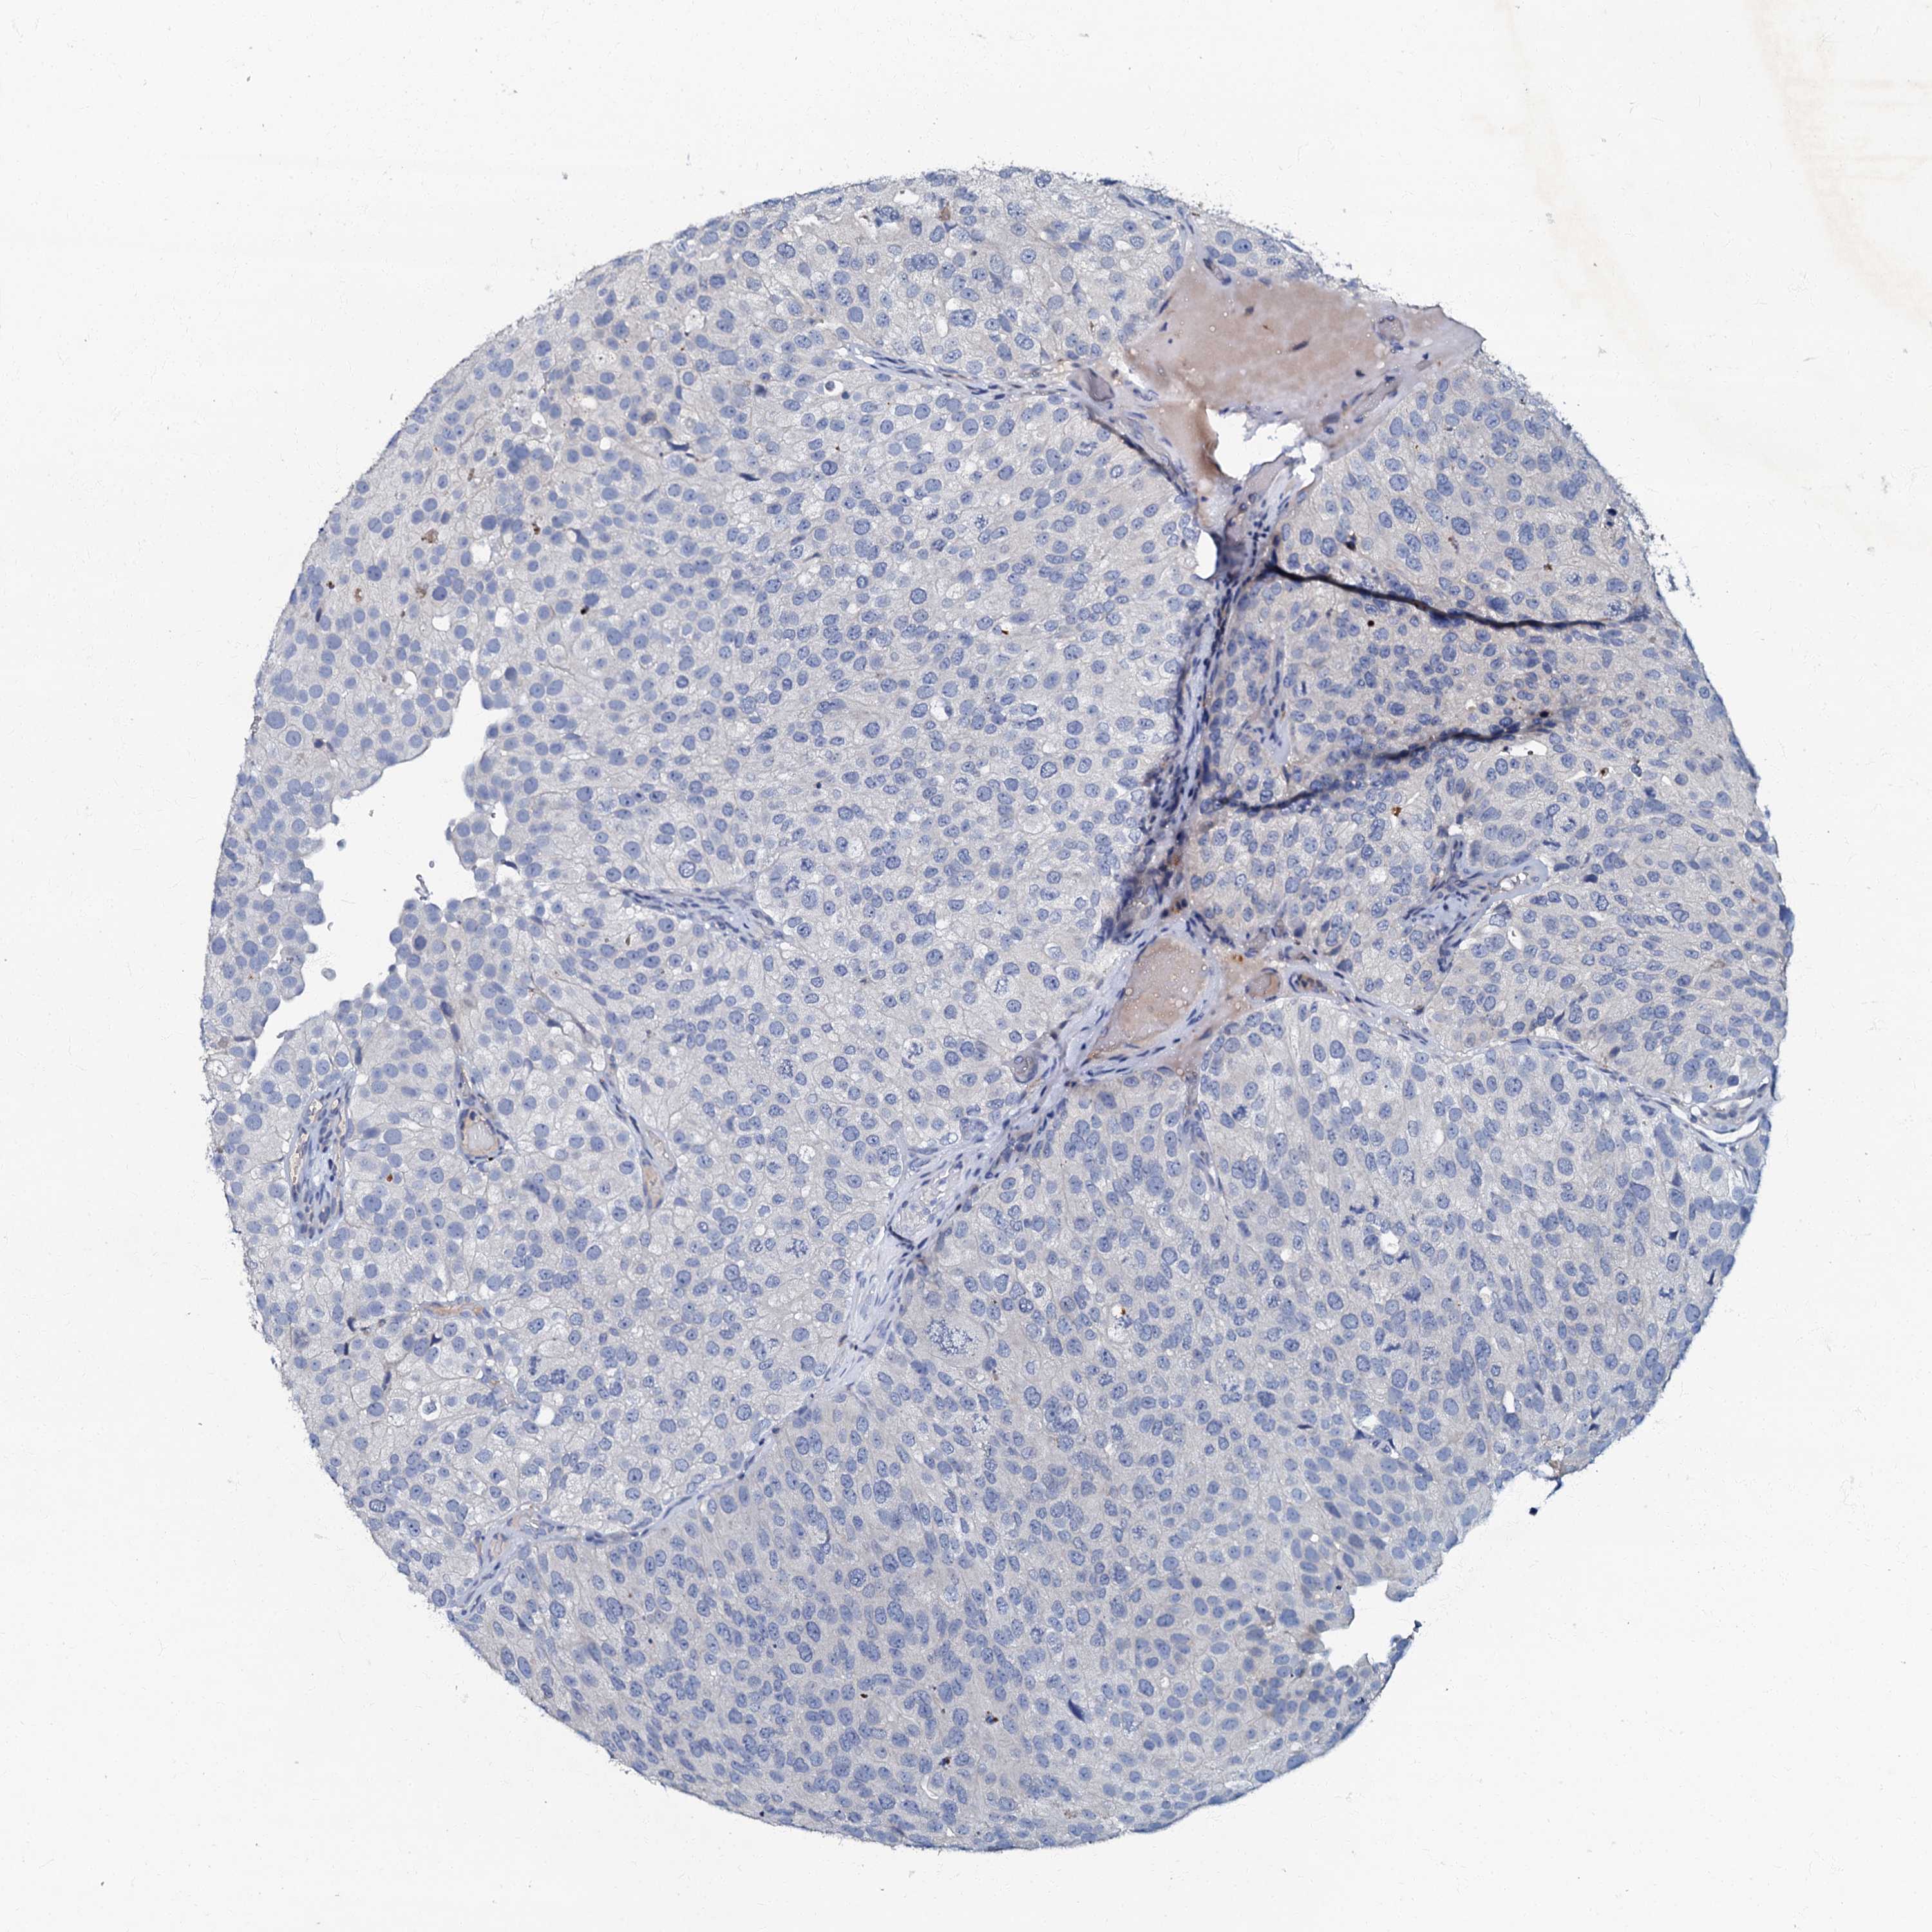

UROTHELIAL CANCER - Protein expressioni

A mouse-over function shows sample information and annotation data. Click on an image to view it in a full screen mode. Samples can be filtered based on level of antibody staining by selecting one or several of the following categories: high, medium, low and not detected. The assay and annotation is described here.

Note that samples used for immunohistochemistry by the Human Protein Atlas do not correspond to samples in the TCGA dataset.

Antibody stainingi

Antibody staining in the annotated cell types in the current human tissue is reported as not detected, low, medium, or high, based on conventional immunohistochemistry profiling in selected tissues. This score is based on the combination of the staining intensity and fraction of stained cells.

Each image is clickable and will lead to virtual microscopy that enables deeper exploration of all samples and also displays staining intensity scores, fraction scores and subcellular localization as well as patient and tissue information for each sample.

Antibody HPA037947

Antibody HPA037948

Staining

High

Medium

Low

Not detected

Intensity

Strong

Moderate

Weak

Negative

Quantity

>75%

75%-25%

<25%

None

Location

Nuclear

Cytoplasmic/membranous

Cytoplasmic/membranous,nuclear

Urothelial carcinoma, High grade

Urothelial carcinoma, Low grade

Urothelial carcinoma, NOS